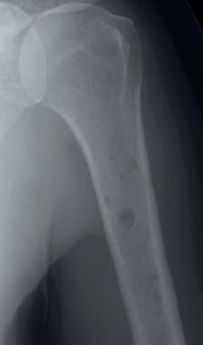

Рентгенограмма. Литический очаг в бедренной кости.

Рентгенограмма. Множественная миелома плечевой кости.